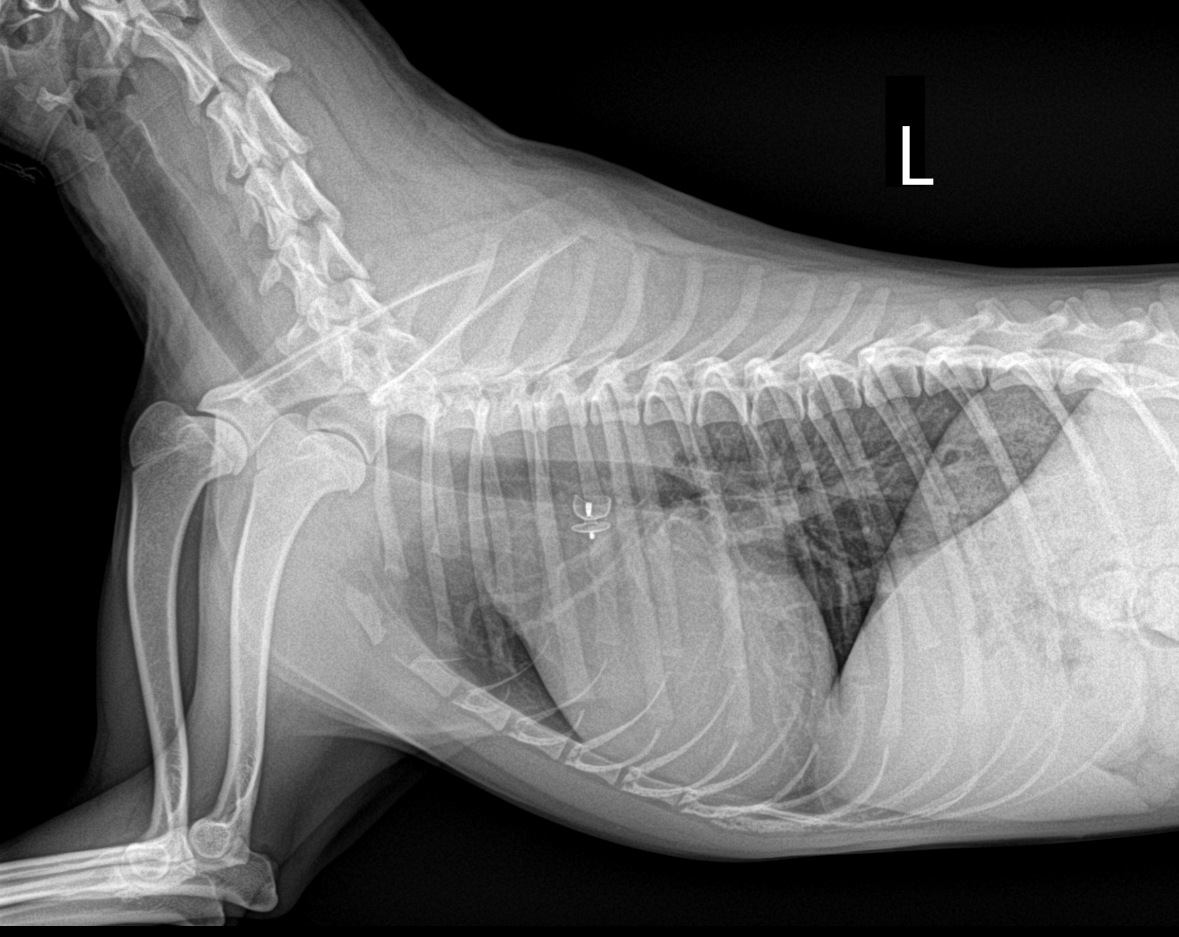

PDA 환자 시술 전후 방사선 비교

시술 전

동맥관 개존증으로 인한 비정상적인 혈류